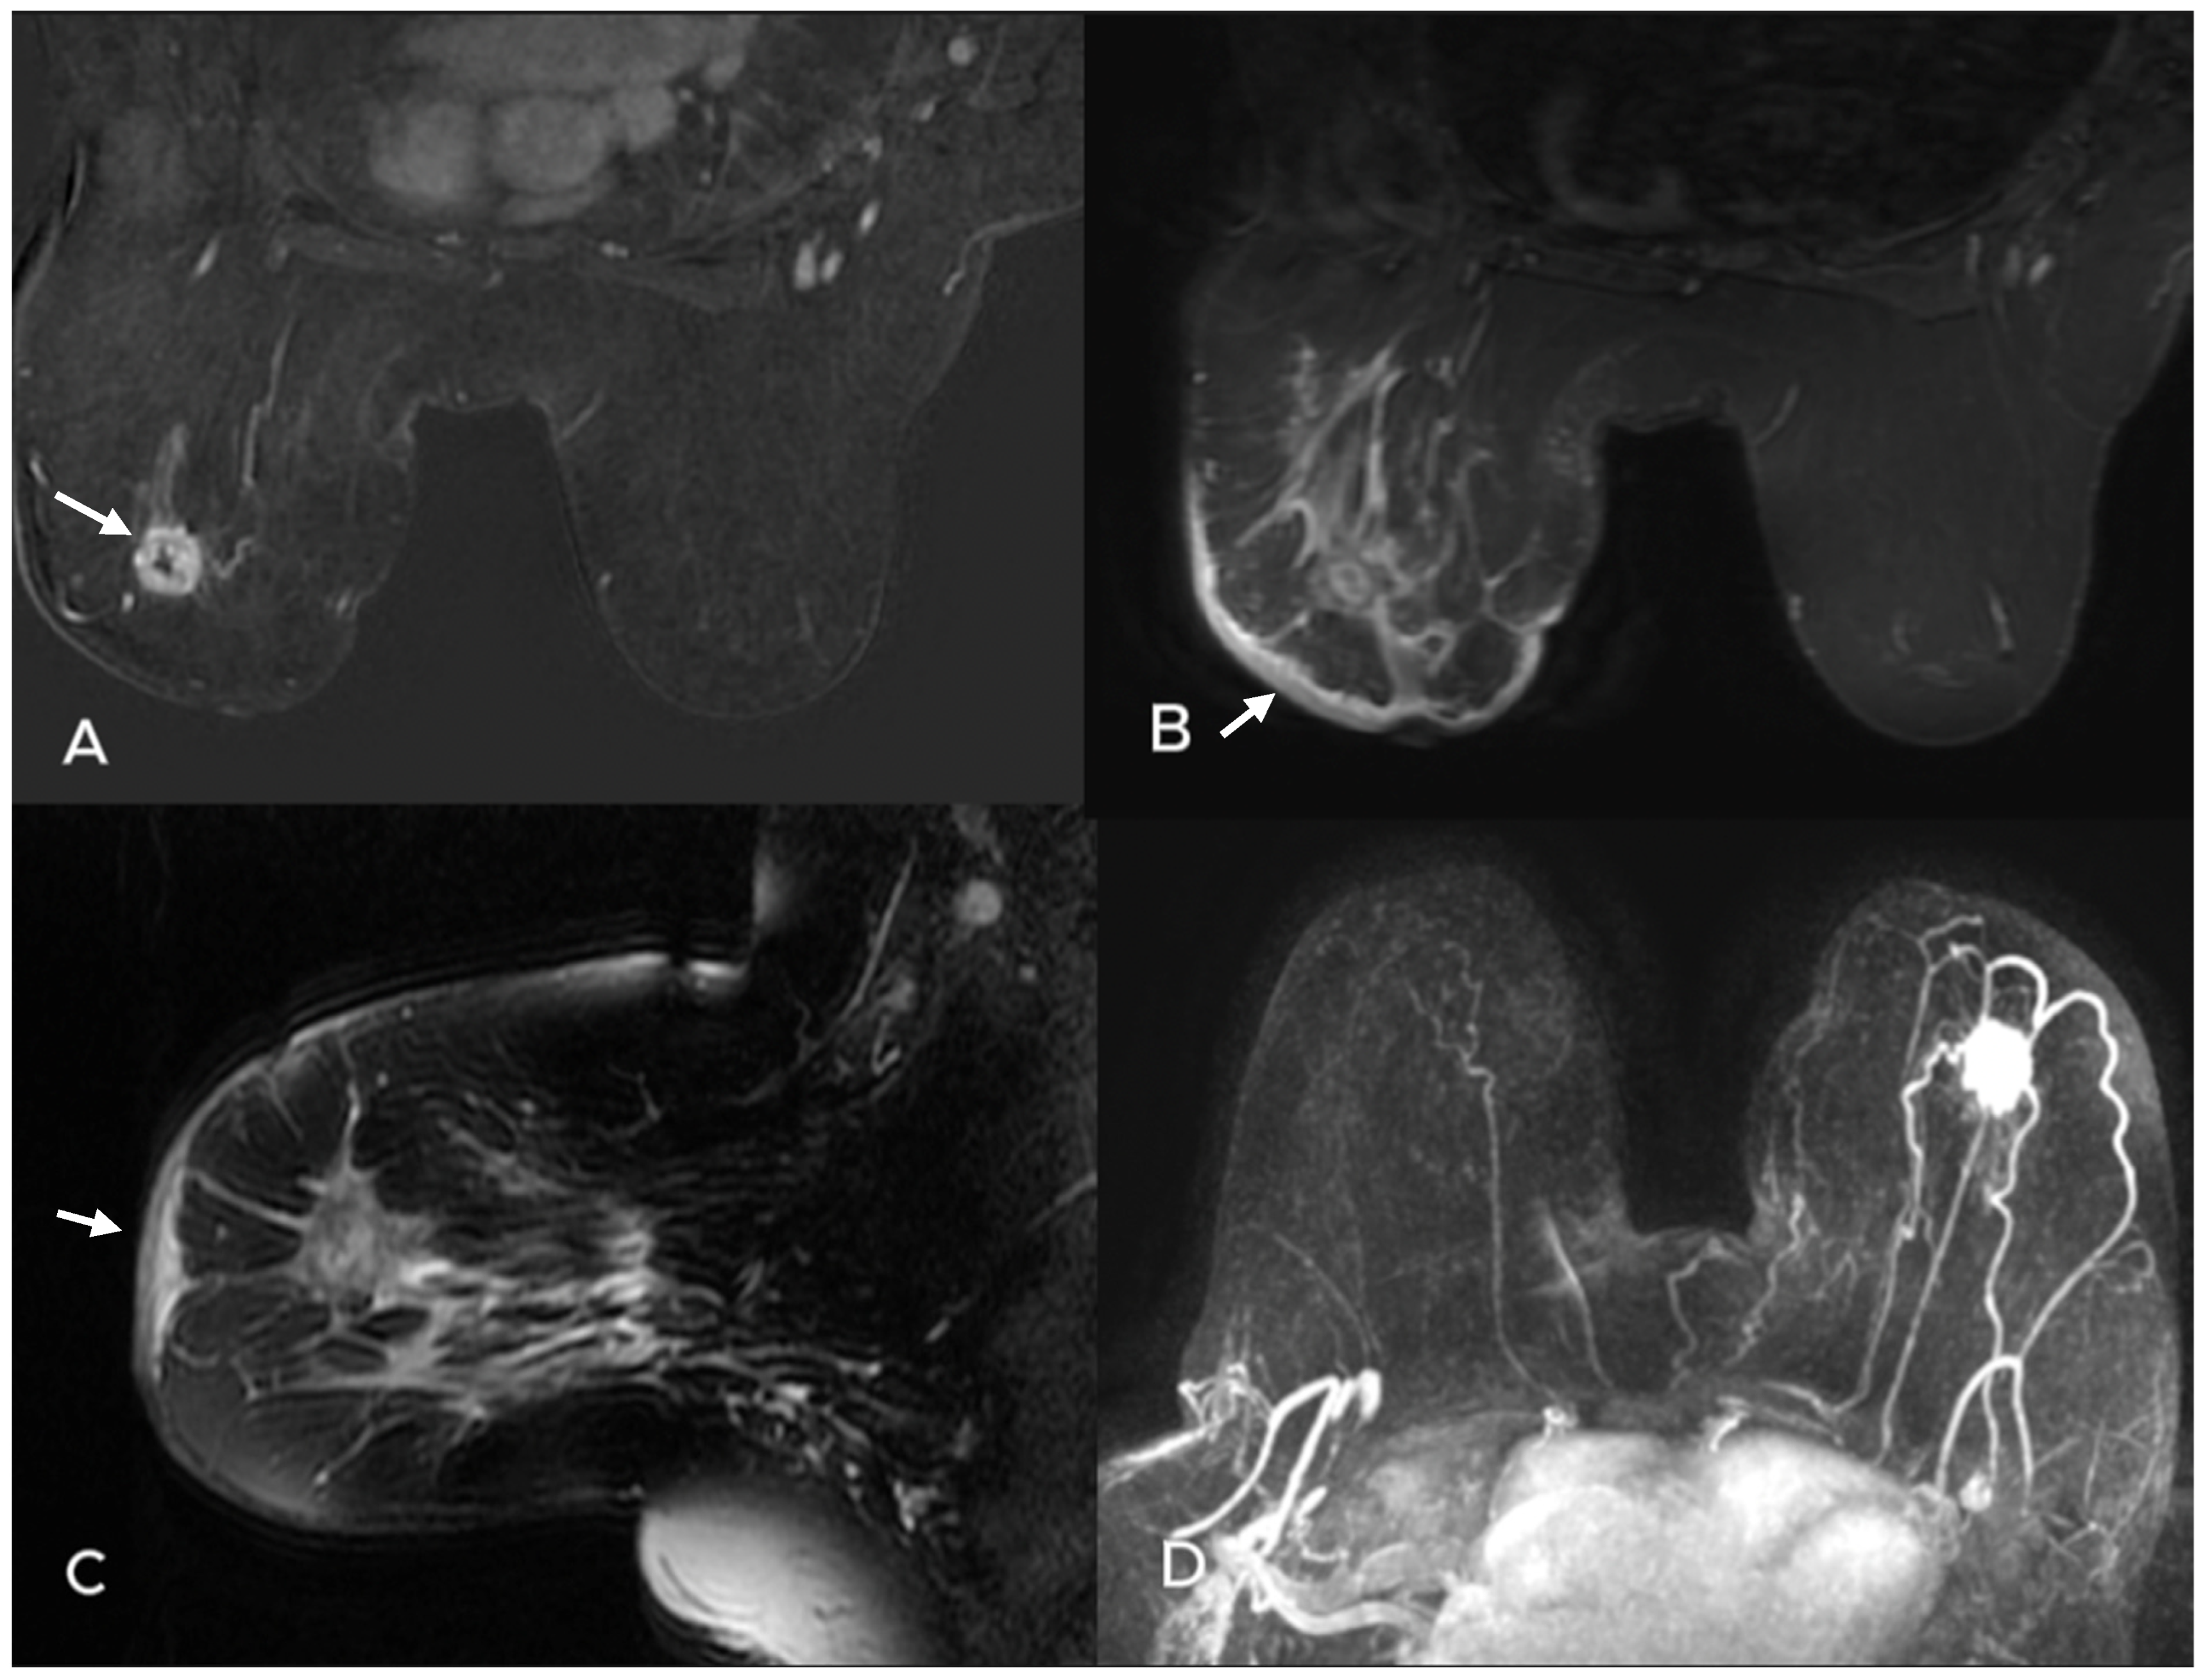

- Uematsu, T. Focal breast edema associated with malignancy on T2-weighted images of breast MRI: Peritumoral edema, prepectoral edema, and subcutaneous edema. Breast Cancer 2015, 22, 66–70. [Google Scholar] [CrossRef]

- Akdoğan Gemici, A.; Tokgoz Ozal, S.; Hocaoğlu, E.; Arslan, G.; Sen, E.; Altınay, S.; İnci, E. Relation of peritumoral, prepectoral and diffuse edema with histopathologic findings of breast cancer in preoperative 3T magnetic resonance imaging. J. Surg. Med. 2019, 3, 49–53. [Google Scholar]

| Number of lesions n (%) | 0.001 * | ||

| Single | 26 (74.3) | 37 (42.0) | |

| Multifocal | 6 (17.1) | 22 (25.0) | |

| Multicentric | 2 (5.7) | 21 (23.9) | |

| Diffuse | 1 (2.9) | 8 (9.1) | |

| Presence of edema n (%) | 0.001 * | ||

| None | 17 (48.6) | 14 (15.9) | |

| Peritumoral edema | 14 (40.0) | 43 (48.9) | |

| Diffuse edema | 4 (11.4) | 31 (35.2) | |